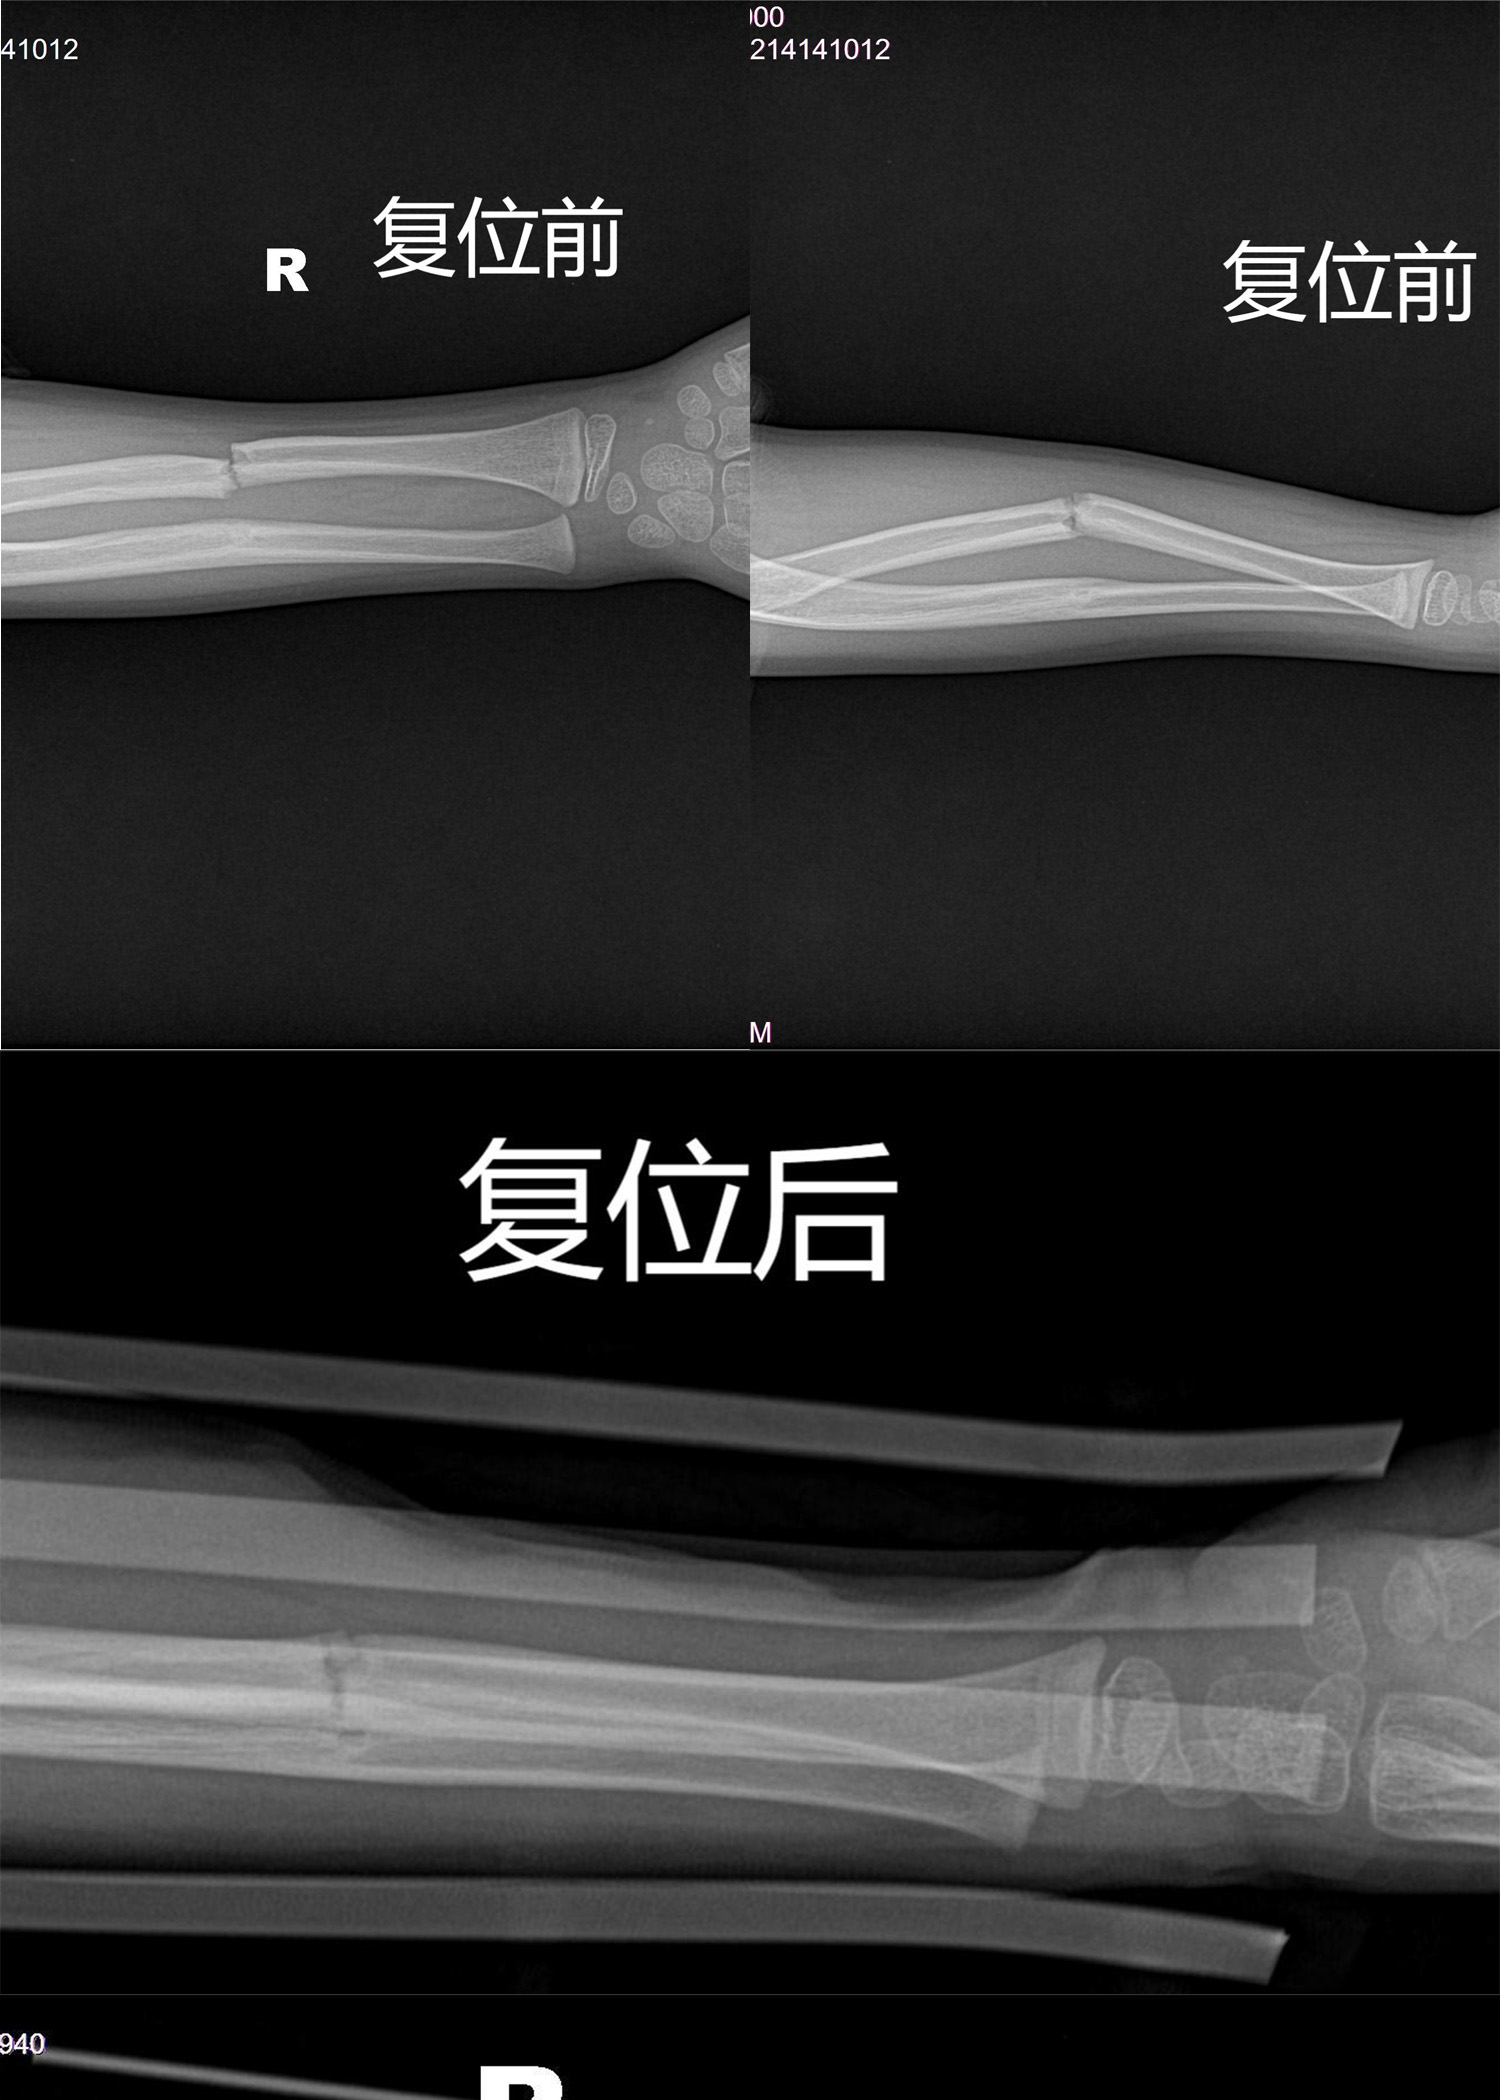

梁氏正骨-梁俊超正骨案例